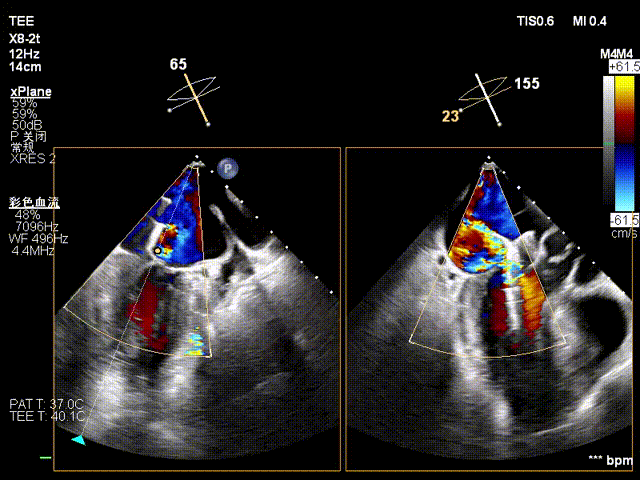

在全麻下,于心尖入路完成ValveClamp®装置植入。术中多学科团队密切配合,超声全程实时指导操作。最终,于2偏3区成功植入一枚Ⅲf夹子,一次夹合完成。前叶夹合量12mm,后叶夹合量10mm,反流降至1+,导管操作时间30分钟。术后平均跨瓣压差3mmHg。

术前反流 术后反流